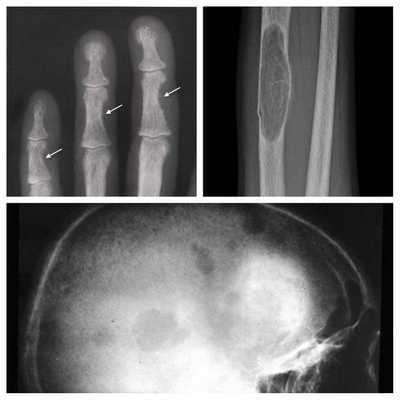

Длительное течение заболевания сказывается на формировании костей. Так, н а поздних стадиях вовремя не диагностированного гиперпаратиреоза наблюдаются:

- разрушение дистальных или концевых фаланг конечностей;

- сужение дистального отдела ключиц;

- очаги разрушения костей черепа;

- бурые опухоли длинных костей.